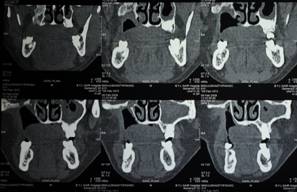

C T SCAN CORONAL SECTION SHOWS THE EXTENT OF DISEASE